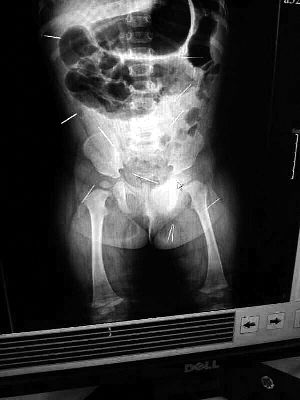

山東聊城11個月女嬰萱萱(化名)疑似被人以12根鋼針插滿臀部、腹腔等部位,昨天在兒童醫(yī)院會診后,醫(yī)生稱3根針靠近胸腔最危險,首批先行取出,預計將在下周二手術。孩子父母稱孩子一直由家人照顧,自家與他人并無冤怨。山東警方表示正在偵破中,不便透露案情。

“要不是當初那幾個紅點,可能到現(xiàn)在我們還不知道孩子身體里有鋼針!”昨天,在兒童醫(yī)院住院處,萱萱爸爸范先生稱,日前原本很愛笑的萱萱突然變得有些焦躁,一抱起來就哭,孩子母親偶然間在萱萱屁股上發(fā)現(xiàn)了幾個小紅點兒,原以為是蚊蟲叮咬,就醫(yī)結果卻讓人不寒而栗?!搬t(yī)院拍出的片子上,萱萱的體內有12根鋼針,插滿臀部、腹腔、骨盆等各個部位?!狈断壬榻B,因為鋼針已深入體內,要是孩子不哭鬧,他們很難發(fā)現(xiàn)。

北京晨報記者了解到,目前體內的12根鋼針多分布在孩子的臀部,一根在腹部,其余3根在胸腔附近,其中一根很接近心臟?!耙驗楹⒆犹。t(yī)生們害怕取針的時候對她造成傷害,在胸腔附近的3針可能會威脅她的生命”。